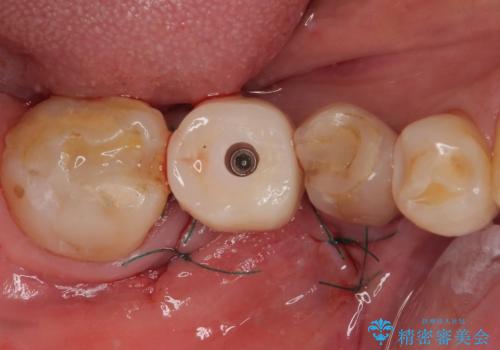

インプラント埋入時に植立具合の安定性を測定したところ、十分な数値が得られたため、速やかに仮歯を装着して咬合回復をさせることができました。

外科処置を1回に抑えることができ、あっという間に治療を終えることができました。